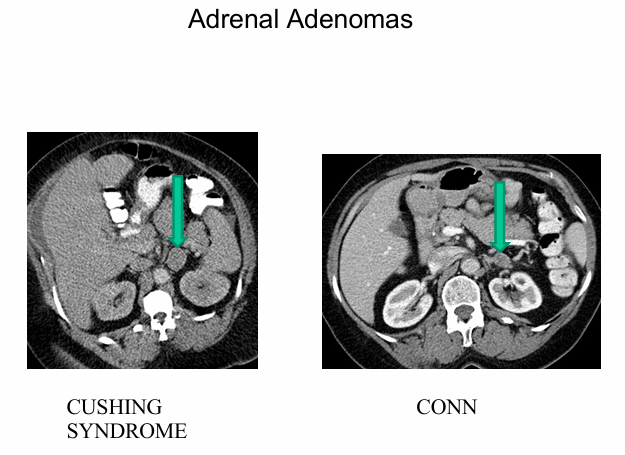

primary aldosteronism

-very common in patients with moderate to severe hypertension

-accounts for 10-20% of resistant hypertension

-40% of cases produced by aldosterone-producing adenoma (usually benign and unilateral)- curable by surgical removal of affected adrenal gland

-60% cases caused by bilateral hyperplasia- responsive to mineralocorticoid antagonists